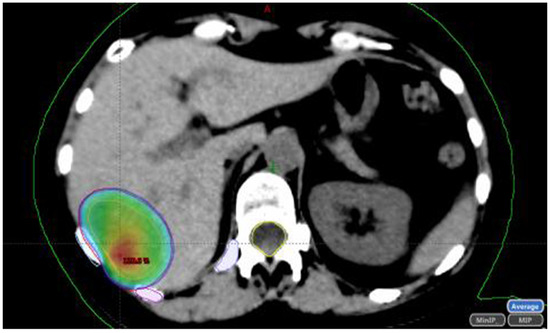

1.2. Stereotactic Body Radiotherapy (SBRT)

1.2.1. SBRT Technique

1.2.2. SBRT Dose

1.2.3. Criteria for Determining SBRT Suitability

1.2.4. SBRT Outcomes

- Consider SBRT to treat lung and liver M1 close to vascular, biliary, or gastrointestinal structures;, laparoscopic ablative treatments also could be considered.